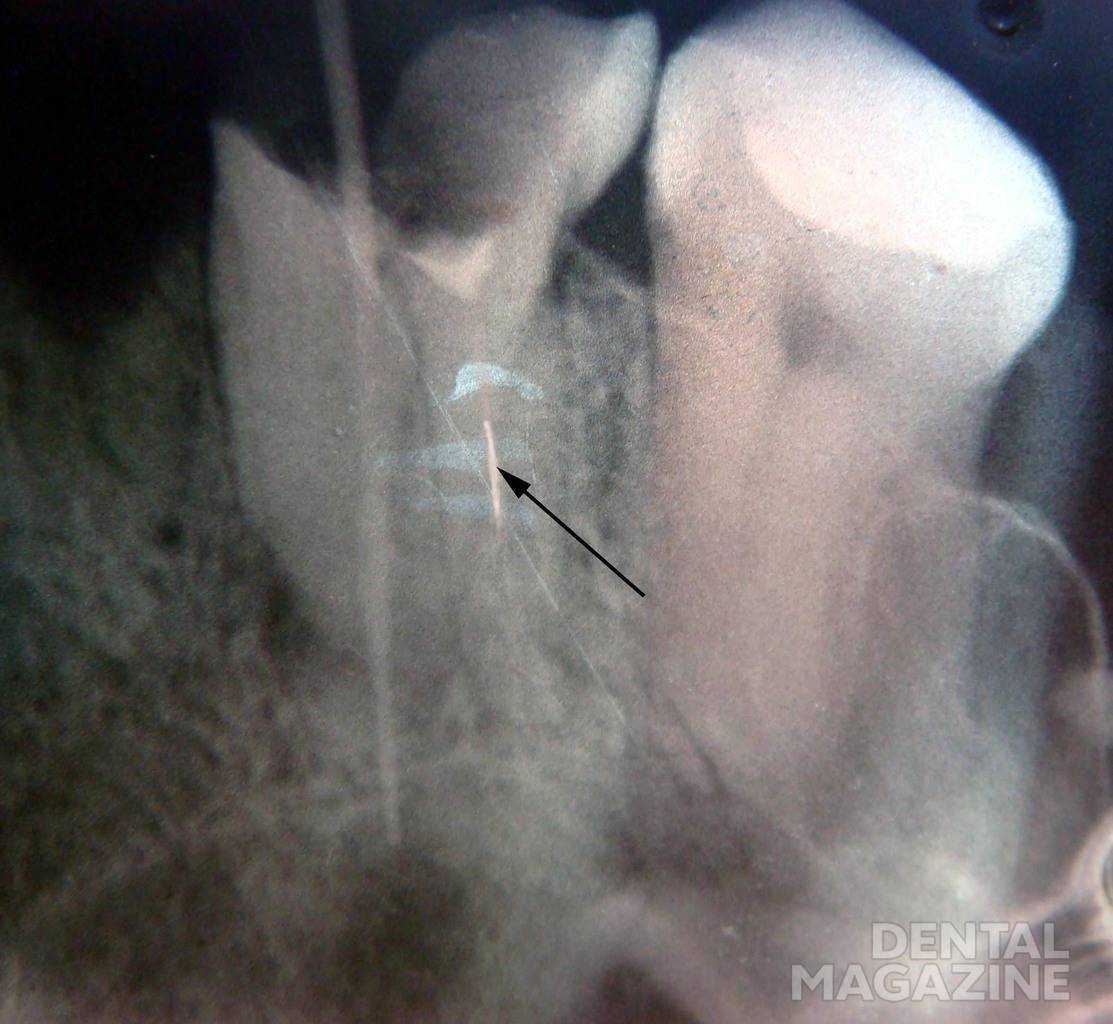

Перелом инструмента в корневом канале

Риск перелома инструмента очень высок в случае деформации файла (изгиба, раскручивания витков) и чаще всего имеет место при прохождении и расширении узких, искривленных, ранее запломбированных каналов (рис. 8). Основными причинами данного осложнения могут стать отсутствие адекватного доступа к устью корневого канала; нарушение последовательности использования эндодонтических инструментов; применение инструментов без учета показаний; несоблюдение режима работы и скорости вращения; приложение значительного усилия при ручной или машинной эндодонтической обработке; усталость металла, обусловленная многократным использованием инструмента.

Рис. 8а. Введение изогнутого файла.

Рис. 8б. Отлом инструмента в корневом канале.

Профилактика поломки инструмента заключается в строгом соблюдении режима работы, использовании инструмента по показаниям. Необходимо учитывать последовательность применения инструментов. В ходе механической обработки рекомендуется использование эндолубрикантов.